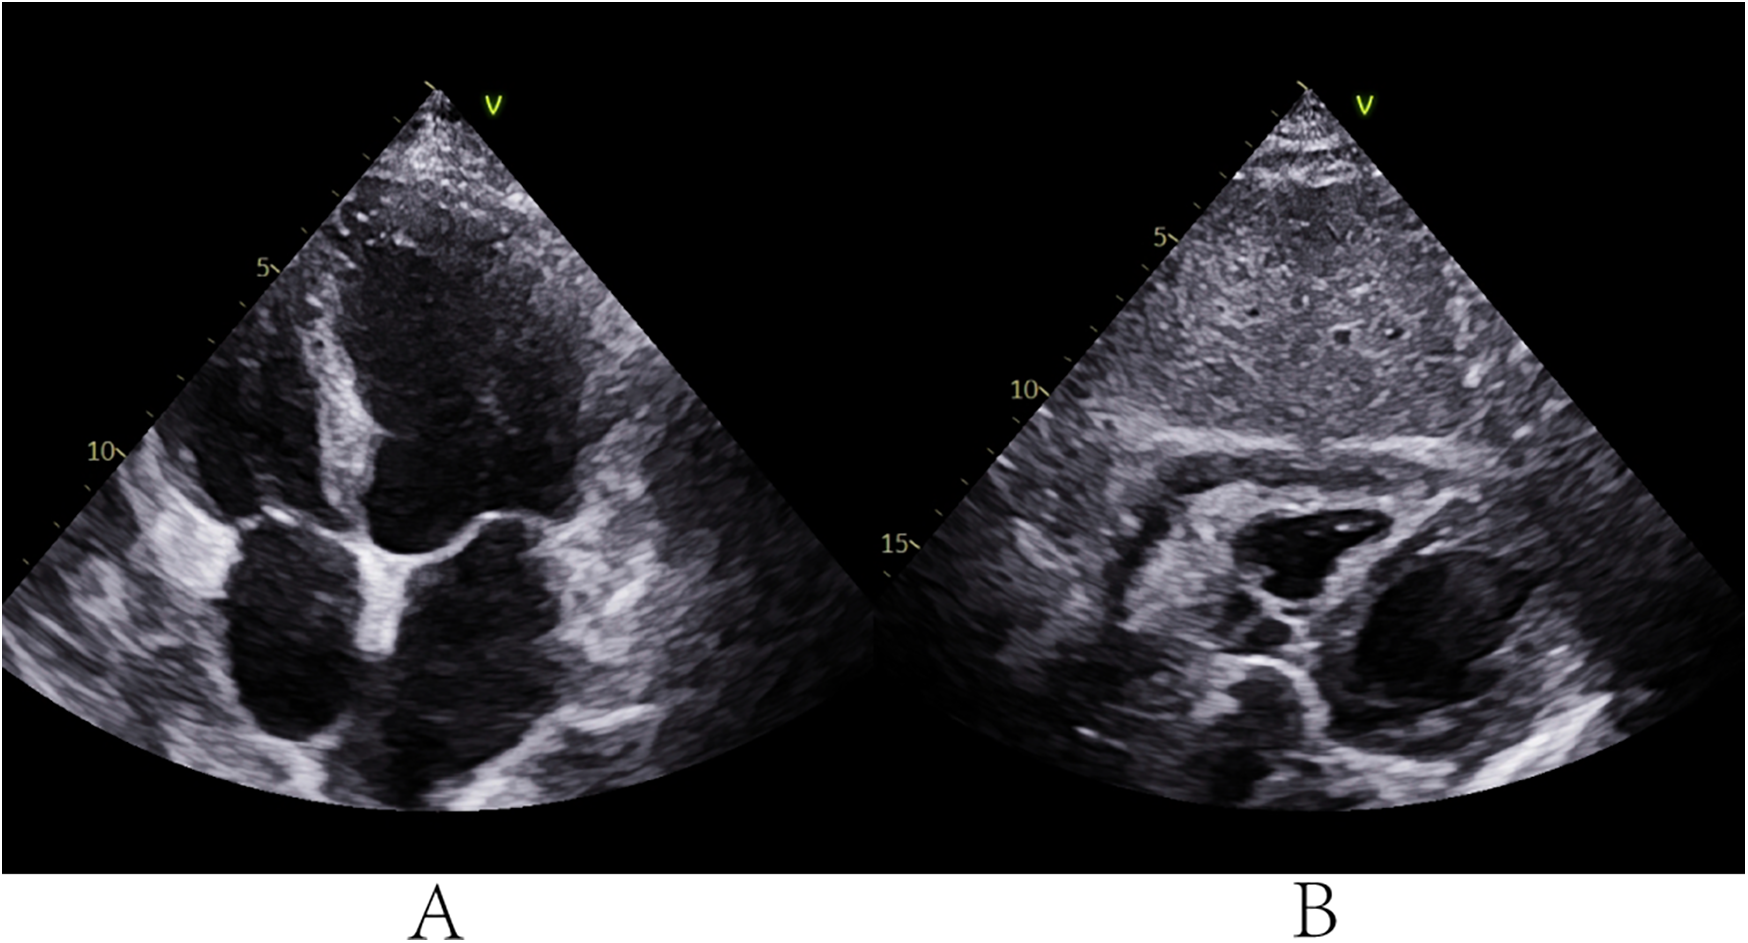

During hospitalization, the patient developed lower limb venous thrombosis, atrial fibrillation, and moderate pleural effusion, which were managed with anticoagulation therapy (low-molecular-weight heparin) and targeted heart failure management. On day 17, persistent dyspnea prompted a repeated TTE, which revealed a loculated gelatinous effusion in the posterior wall of the right pericardial cavity compressing the right atrium and ventricle, with pericardial adhesions (Figures 1A,B and Supplementary Videos S1). Cardiac computed tomography (CT) confirmed pericardial thickening, blurred pericardiophrenic fat planes, and a septated purulent collection adjacent to the right atrium (Figure 1C).

Figure 1

TTE and cardiac CT before PTCA guidewire-based pericardiocentesis. (A,B) TTE revealed a loculated gelatinous effusion in the posterior wall of the right pericardial cavity compressing the right atrium and ventricle, with pericardial adhesions. CT confirmed pericardial thickening, blurred pericardiophrenic fat planes, and a septated purulent collection adjacent to the right atrium.